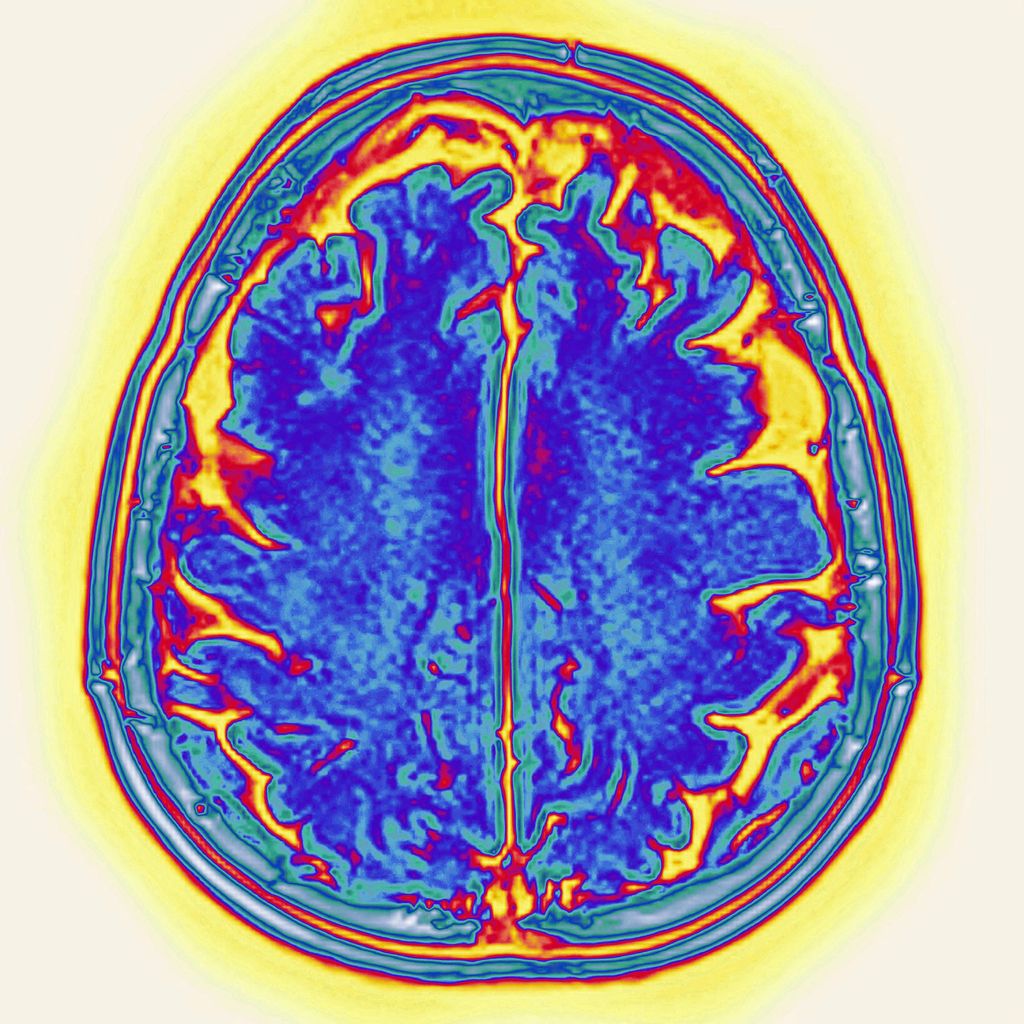

Morbo di Alzheimer

CAVALLINI JAMES / BSIP / BSIP via AFP

- Morbo di Alzheimer